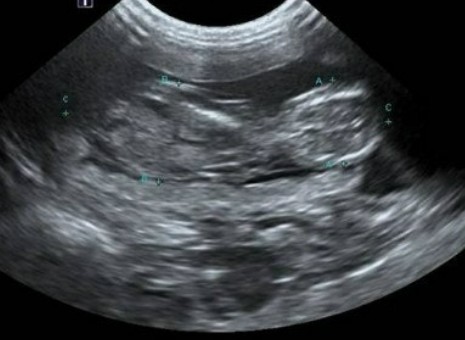

펫 초음파 검사는 고주파 음파를 이용하여 반려동물의 내부 장기를 실시간으로 관찰하는 비침습적 진단 방법입니다. 사람의 초음파 검사와 동일한 원리로 작동하며, 방사선 피폭의 위험이 없어 안전하게 반복 검사가 가능합니다. 초음파는 신체 조직을 통과하면서 각 조직의 밀도에 따라 다르게 반사되는데, 이 반사파를 영상으로 변환하여 장기의 크기, 모양, 내부 구조를 확인할 수 있습니다. 특히 복부 장기인 간, 신장, 비장, 췌장, 방광 등의 상태를 파악하는 데 매우 유용하며, 심장 초음파를 통해서는 심장의 구조와 기능, 혈류 상태까지 정밀하게 분석할 수 있습니다. 엑스레이로는 확인하기 어려운 연조직의 변화나 체액 축적, 종양의 존재 여부를 명확하게 진단할 수 있어 현대 수의학에서 필수적인 검사로 자리잡았습니다. 펫 초음파 검사는 통증이 없고 진정제나 마취가 필요하지 않아 노령 반려동물이나 건강이 좋지 않은 반려동물에게도 안전하게 시행할 수 있습니다. 검사 시간은 일반적으로 20분에서 40분 정도 소요되며, 검사 부위와 목적에 따라 달라질 수 있습니다. 최근에는 초음파 장비의 발전으로 해상도가 크게 향상되어 더욱 정밀한 진단이 가능해졌으며, 일부 동물병원에서는 3차원 입체 영상을 제공하기도 합니다.

펫 초음파 검사는 다양한 임상 증상이 나타났을 때 정확한 진단을 위해 실시됩니다. 구토나 설사가 지속되는 경우 소화기 장기의 이상을 확인하고, 복부 팽만이나 복수가 의심될 때 그 원인을 파악합니다. 혈액 검사에서 간수치나 신장 수치가 비정상적으로 나왔다면 해당 장기의 구조적 변화를 직접 관찰할 수 있습니다. 소변에 혈뇨가 섞여 나오거나 배뇨 장애가 있을 때는 방광과 요도를 검사하여 결석이나 종양의 유무를 확인합니다. 복부에 만져지는 종괴가 있거나 갑작스러운 체중 감소가 나타난 경우에도 펫 초음파 검사를 통해 종양의 위치와 크기, 주변 조직과의 관계를 파악합니다. 임신 진단과 태아의 건강 상태 확인에도 활용되며, 출산 예정일 산정에도 도움을 줍니다.